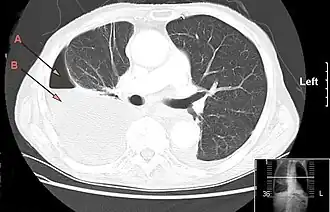

CT-thorax laat een grote rechtszijdige hydro-pneumothorax zien, ontstaan door empyeem. Pijl A: lucht, B: vocht | ||||